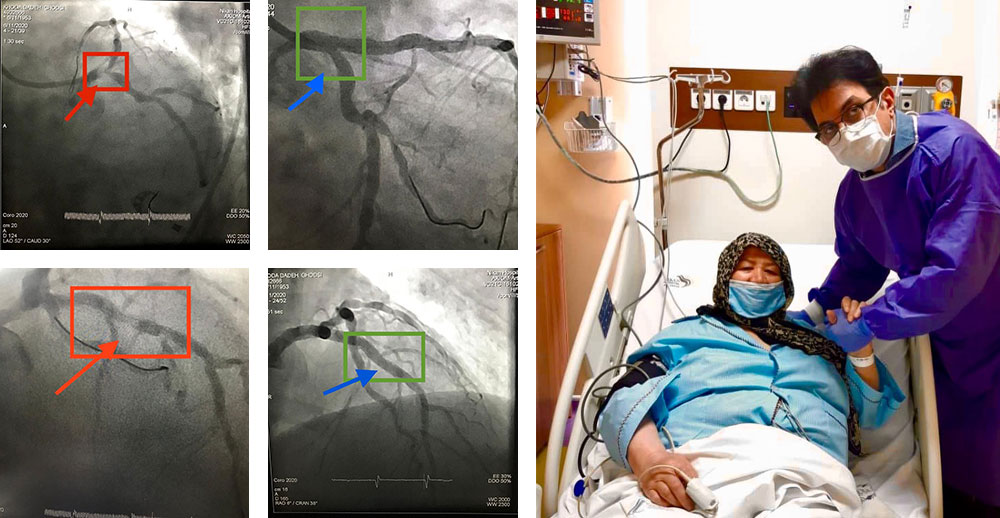

تنگی مدخل ورودی سیستم چپ عروق قلب

تا همین چند سال پیش راهی جز عمل جراحی اورژانس قلب باز نداشت. بیمار ما روز بعد از کارگذاری سه استنت در سیستم چپ به زندگی دوباره باز می گردد و قابل ترخیص است.

انسداد کامل رگ

انسداد کامل رگ آخرین سنگر ناگشوده ی آنژیوپلاستی بود که با تکنیک های جدید، تا ۹۰٪ امکان بازگشودگی بدون جراحی قلب باز را دارد. بیمار اول انسداد کامل رگ راست و دومی انسداد کامل رگ چپ داشتند. هر دو بیمار از طریق هر دو شریان دست راست وچپ درمان و روز بعد بی هیچ عارضه یی مرخص شدند. ایمان بیاوریم به اعجاز روش های نوین آنژیوپلاستی!

بازکردن رگ اصلی و فرعی بطور همزمان با دو استنت

بیمار عزیز ما با سکته ی قلبی، روز بعد از آنژیوپلاستی با عروق باز شده آماده ی ترخیص است.